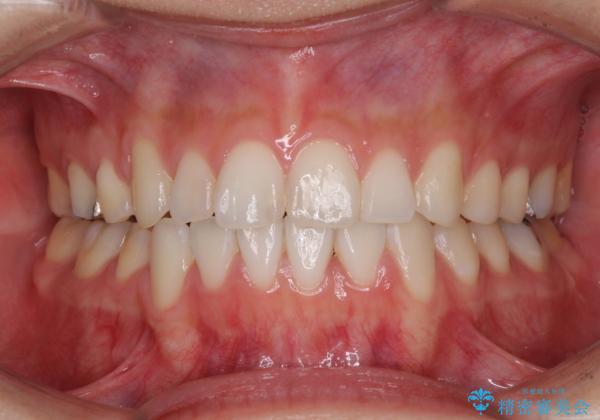

- 上下の八重歯を気にして来院された患者様です。

上下ともに八重歯の後ろの歯を1歯ずつ抜歯し、補助装置(リンガルアーチ)を用いて八重歯の位置を改善し、その後インビザラインにより矯正治療を行うこととしました。

途中海外留学をされたため、治療期間は長くなりましたが、事前に補助装置やワイヤー装置を併用したことで、きれいな歯列に仕上げることができました。